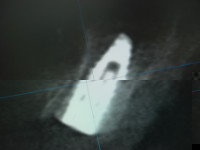

臼歯部、前歯部共にスプリットクレスト、GBRしての埋入でしたね。